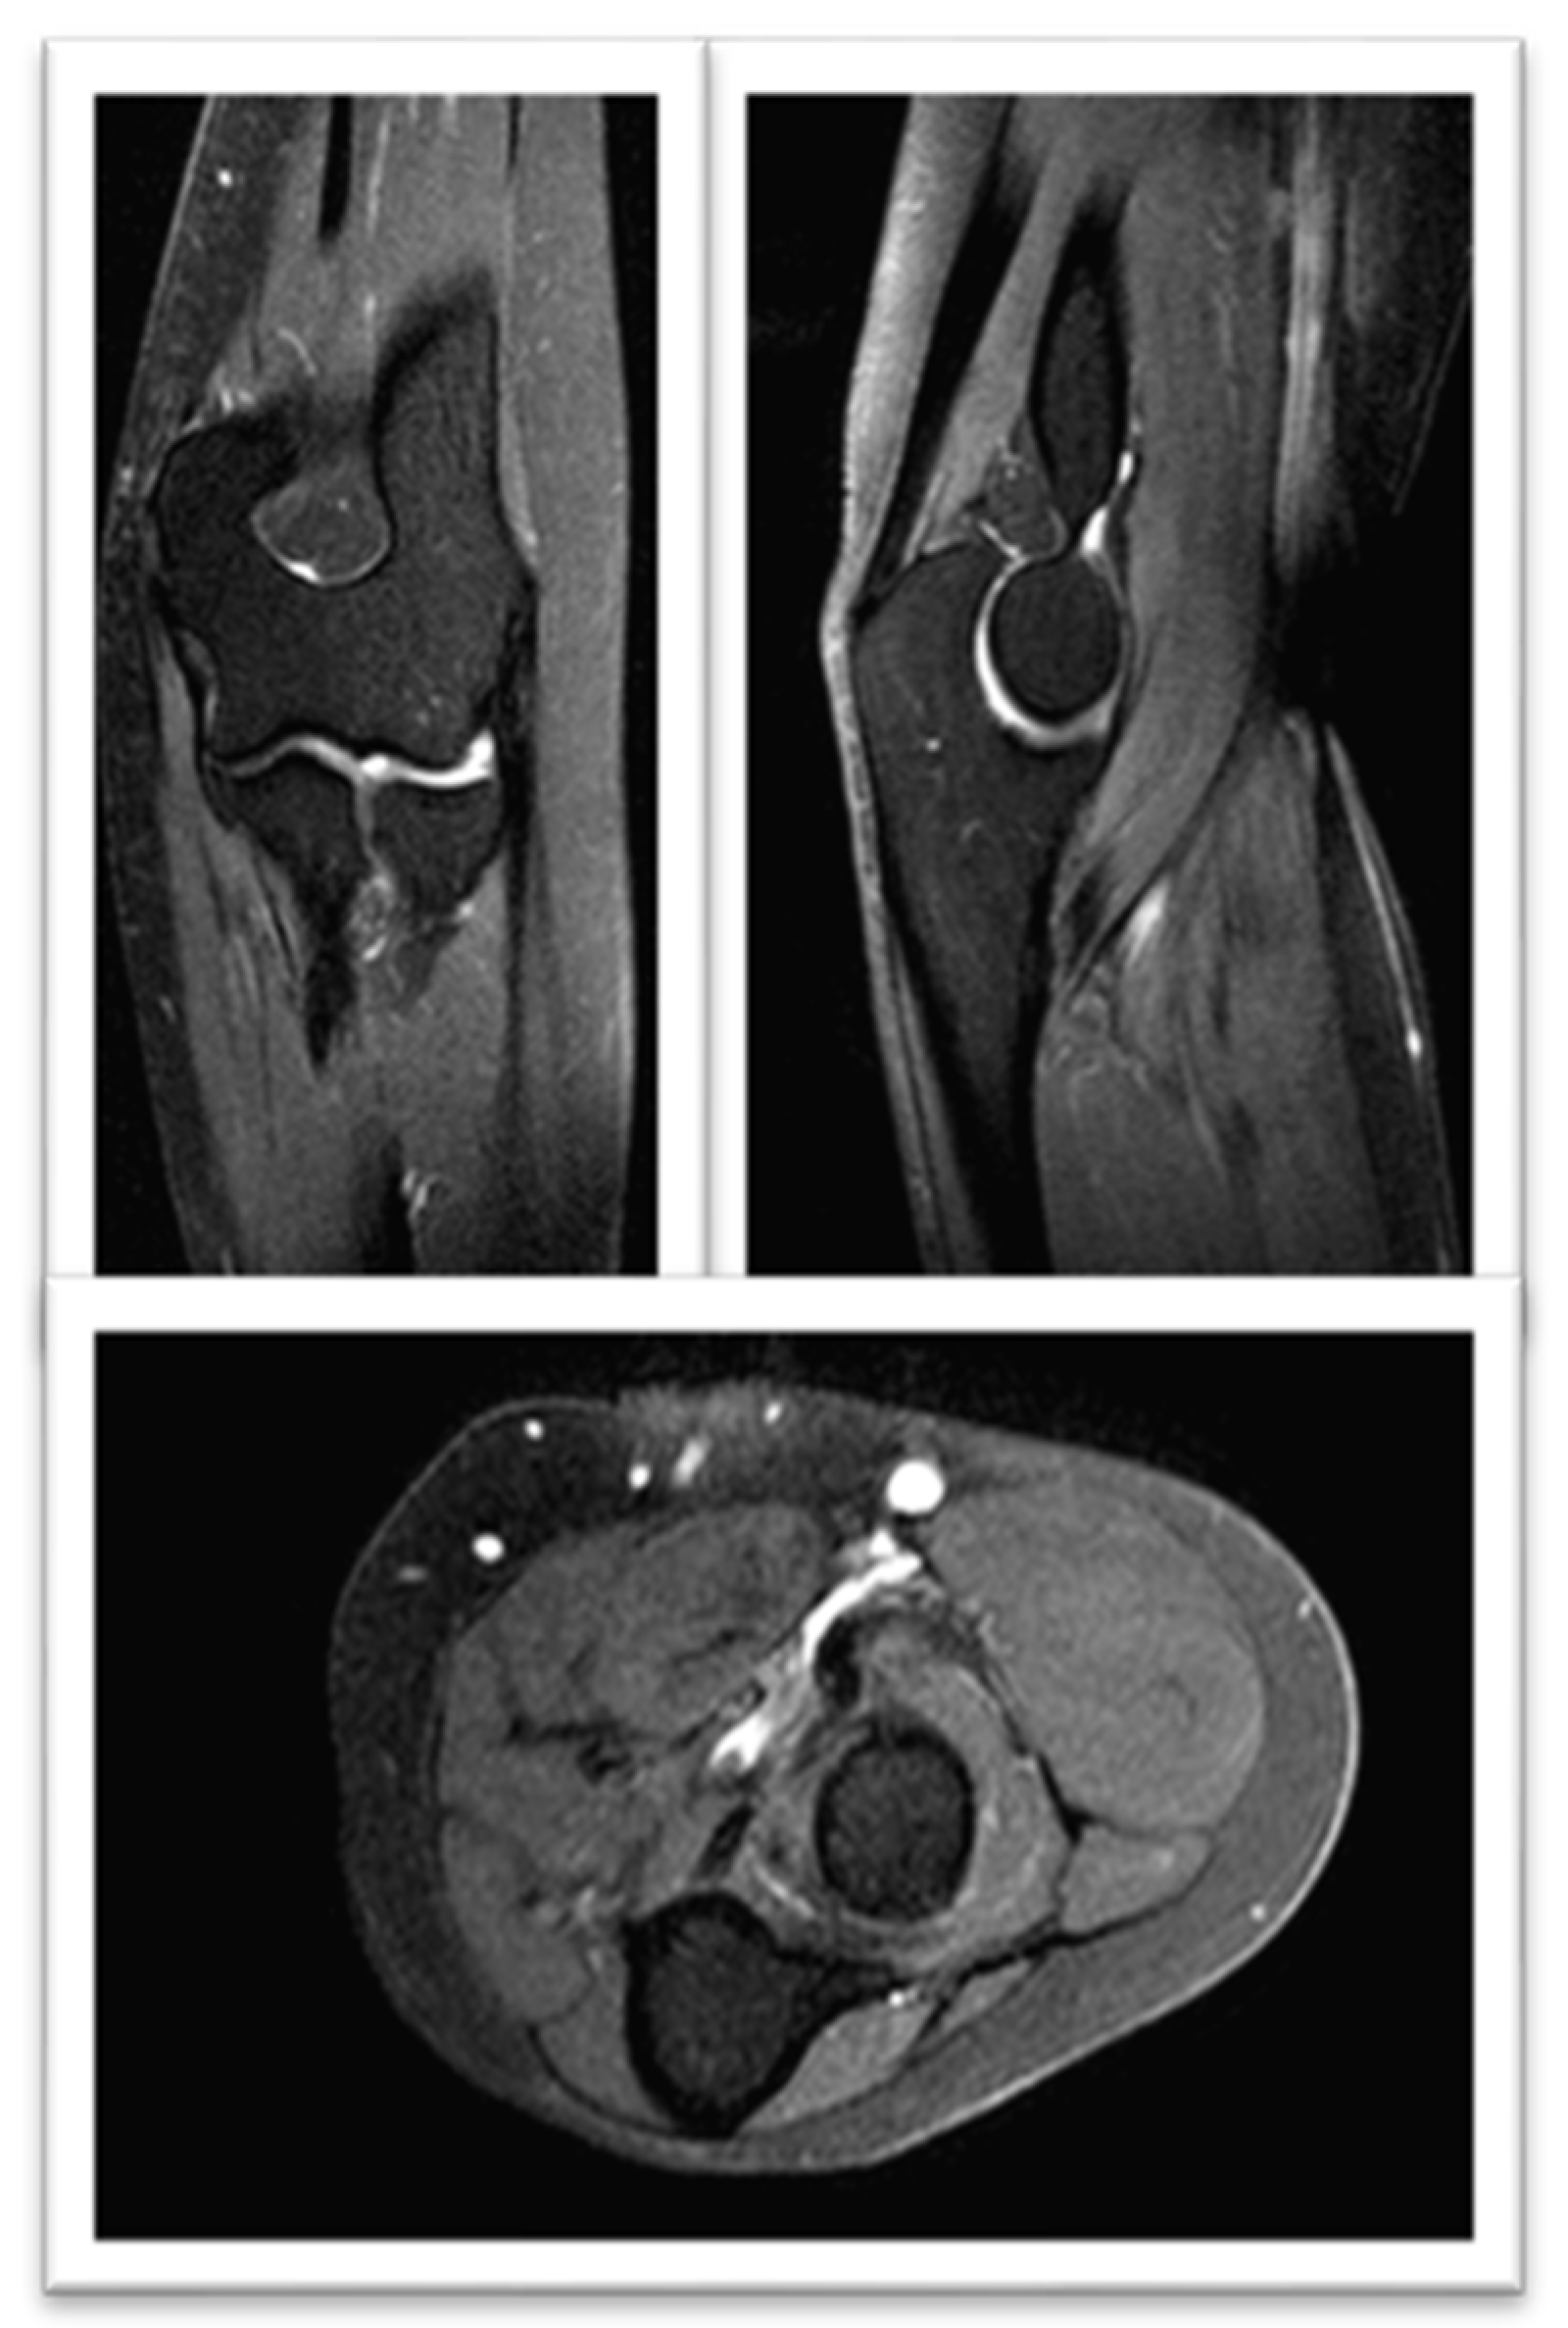

- Pinal-Fernandez, I.; Casal-Dominguez, M.; Carrino, J.A.; Lahouti, A.H.; Basharat, P.; Albayda, J.; Paik, J.J.; Ahlawat, S.; Danoff, S.K.; Lloyd, T.E.; et al. Thigh muscle MRI in immune-mediated necrotising myopathy: Extensive oedema, early muscle damage and role of anti-SRP autoantibodies as a marker of severity. Ann. Rheum. Dis. 2017, 76, 681–687. [Google Scholar] [CrossRef]